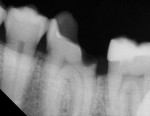

TheraCal™ LC can also be used for indirect pulp capping. Infected soft dentin under a previously placed restoration was removed, leaving affected dentin that could easily be cleaned with CAVITY CLEANSER™ (2% chlorhexidine, BISCO) (Figure 3).

Radiographic interpretation shows the close approximation of an asymptomatic pulp (Figure 4). TheraCal LC was placed onto moist dentin in up to 1-mm increments and immediately light-cured. ALL-BOND SE® (BISCO) was subsequently placed to bond CORE-FLO™ DC (BISCO) as a base/core (Figure 5). Both TheraCal LC and CORE-FLO DC are radiopaque, allowing these materials to be easily identified on radiographs (Figure 6).